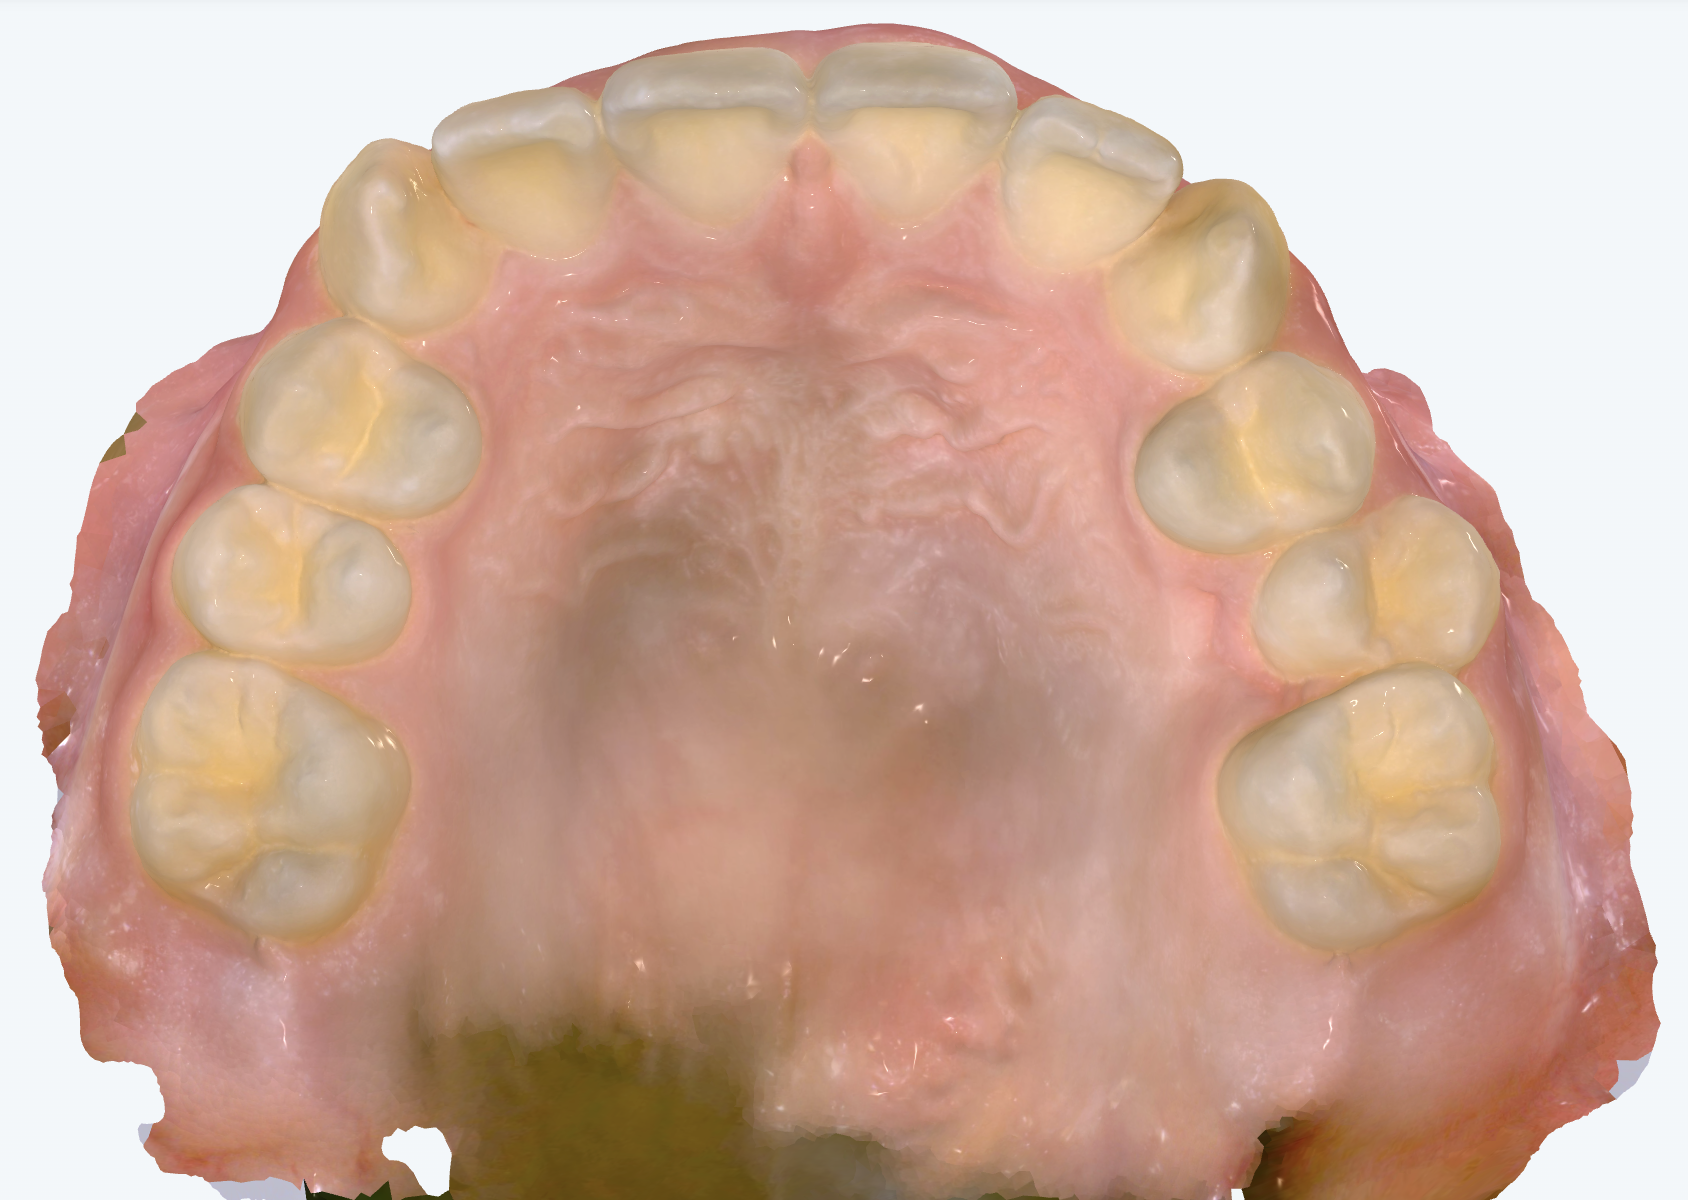

初診時の画像診断

下の左右の前から2番目の歯がもともとありません(先天欠如)。

そうですね。実際、T.Mさんの場合は下の前歯が2本先天的に欠損しているという特徴があります。歯が足りない分、スペースが生まれてガタつきは少ないのですが、上下の歯の本数が合わないことで、かみ合わせや歯の傾きに影響が出ていますね。

下の歯が足りないため、上の前歯がなんとか噛もうと手前に大きく傾いています。そのため噛み合わせが深くなったり、前歯の出っ歯感が強調されています。奥歯のかみ合わせ自体はとても良好なので、前歯の本数を上下で合わせるために、上の歯(小臼歯)を1本抜いて本数をそろえるというのが治療方針の選択肢になります。そうすることで、上の前歯の傾きを正しい位置に整えながら、上下で自然に噛み合うようにしていくことが重要になります。